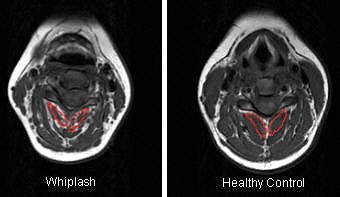

For the image analysis, regions of interest (ROI) were drawn over each bilateral cervical extensor muscle on the axial T1-weighted images at each vertebral segment (C0-C7). The authors also tested the reliability of MRI in this setting.

| T1-weighted MRI axial slice of the C4 segmental musculature (multifidus muscle outlined in red). |

According to the results, MRI showed a higher level of fat within all extensor muscles in the WAD group. Also in this group, the multifidus muscle showed significantly higher fat content at each level. The largest amounts of intramuscular fat were pinpointed in the rectus capitis posterior minor and major, and the deep cervical multifidi muscles, the authors stated.

"The higher levels of fatty infiltrate in the suboccipital ... and multifidus muscles ... could lead to the contention that there was a greater injury with consequent change in the muscles at these segments. It is possible that those with upper cervical injuries may be more prone to chronicity," the group explained, adding that some of the symptoms associated with WAD -- headache, unsteadiness -- are associated with upper cervical structures.